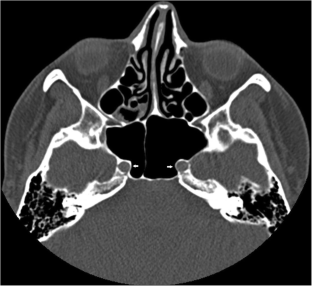

Fig. 1